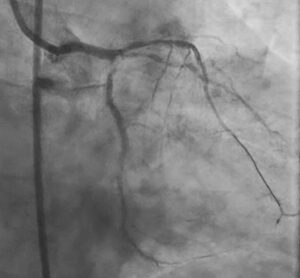

Final Result: Good Stent Expansion on IVUS

After stent implantation, post-PCI IVUS confirmed good stent expansion.

Good expansion in this setting reflects the value of the entire procedural sequence:

wire escalation, failed crossing attempts, atherectomy, imaging-guided assessment, additional scoring balloon modification, supported stent delivery, and final IVUS optimization.

Staged LM Bifurcation PCI